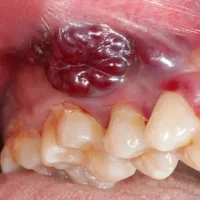

Tumeurs bénignes de la cavité buccale

Lésions et tumeurs buccales

Érythroplasie